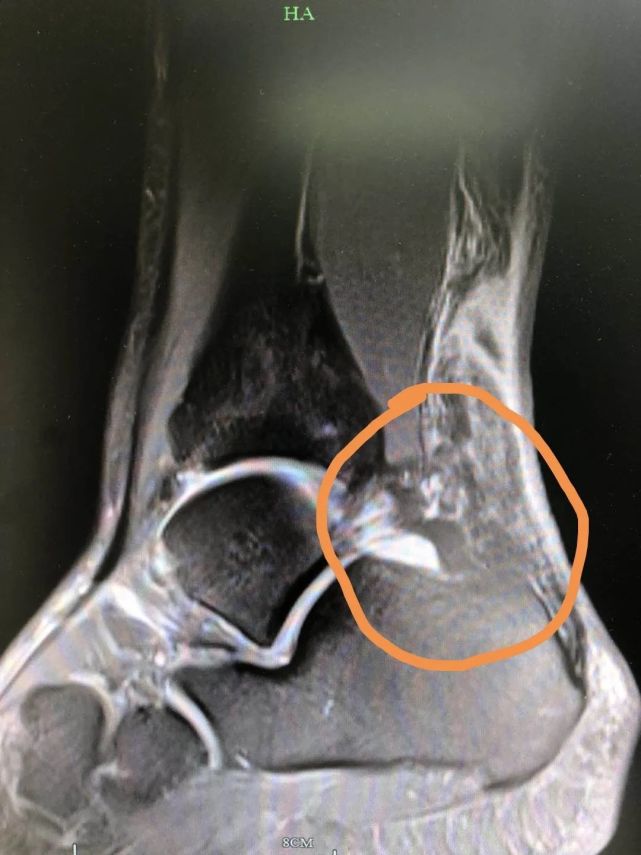

诊断为:左侧跟腱断裂.mri显示为肌腱与肌肉移行部的撕裂,为高位撕裂.